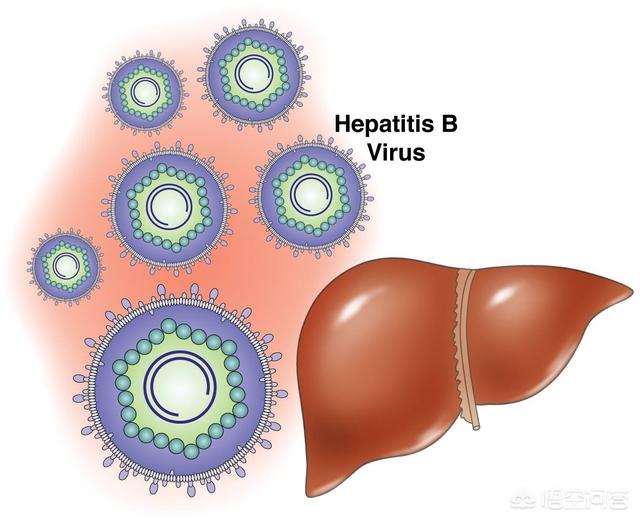

1.肝炎

B/C型肝炎、肝硬変、肝癌は、中国における肝癌発症の最も重要な3部作である。欧米先進国の肝臓がんは、アルコール性肝炎、肝硬変、肝臓がんが主な原因であり、原因は似ている。肝炎による肝細胞へのダメージがある程度蓄積されると、発がんのリスクが高くなる。

中国では、肝炎→肝硬変→肝がんの3部作が存在する。海外で最も一般的なものはアルコール誘発性肝硬変。

もし肝硬変を基礎疾患とするB型肝炎の既往歴は、肝癌のハイリスク群である。画像所見で疑わしい部位やαフェトプロテインの上昇を伴う場合は、がんが存在する可能性がある。

医学統計によると、中国の原発性肝臓癌の90%以上はHBsAg陽性のB型肝炎患者である。また、B型肝炎患者は定期的にアルファフェトプロテイン指数と肝臓超音波検査を再検査する必要があり、肝臓癌の早期発見の確率を高めることができる。

3.B型慢性肝炎:中国ではB型肝炎ウイルスキャリアは10%に達し、肝臓がんの80%はB型慢性肝炎が原因である。肝細胞癌は慢性B型肝炎と密接な関係があり、肝炎、肝硬変、肝細胞癌は肝臓三部作と呼ばれている。B型慢性肝炎の患者さんは、定期的に肝機能とB型肝炎ウイルスDNA定量を見直し、抗ウイルス薬を内服してウイルス価を正常にする必要があります。B型慢性肝炎のハイリスク・リスク背景とハイリスク・リスク年齢段階の人々にとって、早期肝がんの定期的なスクリーニングは、傷害保険に加入し、6ヵ月ごとにチェックすることと同じである。AFP+肝臓、胆嚢、脾臓B超これにより、少なくとも80%の肝臓がんを2-125px以内に検出することができる。

- 肝硬変は肝がんの前がん病変である。わが国が世界有数の肝がん大国であるのは、B型肝炎大国であることに由来する。B型慢性肝炎は最も危険な要因です。世界では毎年約60万人が新たに肝臓がんに罹患しており、その80%が中国で発生している。B型肝炎ウイルスに感染すると慢性肝炎になり、肝硬変、そして肝臓癌へと進行する。B型肝炎は肝炎→肝硬変→肝がんの "3ステップ "で肝がんに至る。